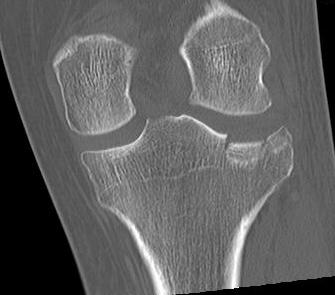

3 column concept of tibial plateau fractures

Luo et al. Orthop Trauma 2010

- introduces the 3 column concept

- medial column / lateral column / posterior column

- posterior column can be splint into medial and lateral fragments (posterolateral / posteromedial)

- imporant as any surgery must address these fragments

- typically require additional posteromedial or posterolateral approaches